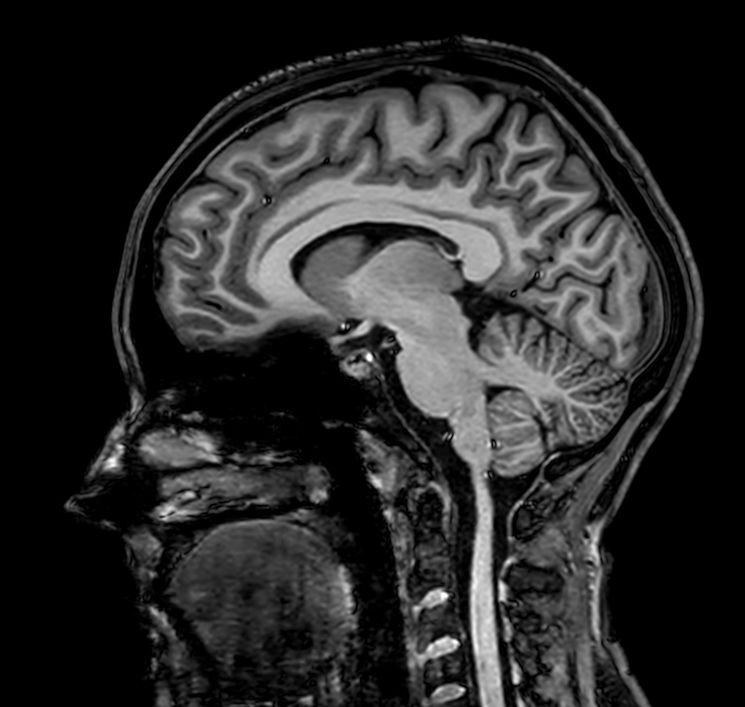

Sagittal 3D T1w TFE

Fast and high quality 3D imaging for Brain and IAC. AI based SmartSpeed is utlized to shorten scan time without compromise in image quality. Advanced 3D TSE imaging technique are used to acquire high resolution data in multiple directions in only one single scan. Addition of DRIVE enhances fluid visualization for IAC imaging, while providing high contrast-to-noise and high signal-to-noise ratio simultaneously. SWIp 3D susceptibility weighted brain imaging is added, offering a high sensitivity to enhance contrast for deoxygenated (venous) blood or calcium deposits.